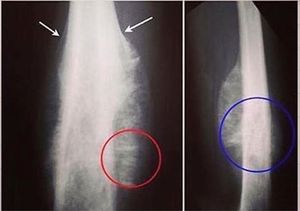

Ewings sarcoma

Ewings characteristing codmans triangle or am i wrong?

Ur right brother 🙌

It has a onion periosteal apearance

Yeah thts is the main sign of ewing sarcoma